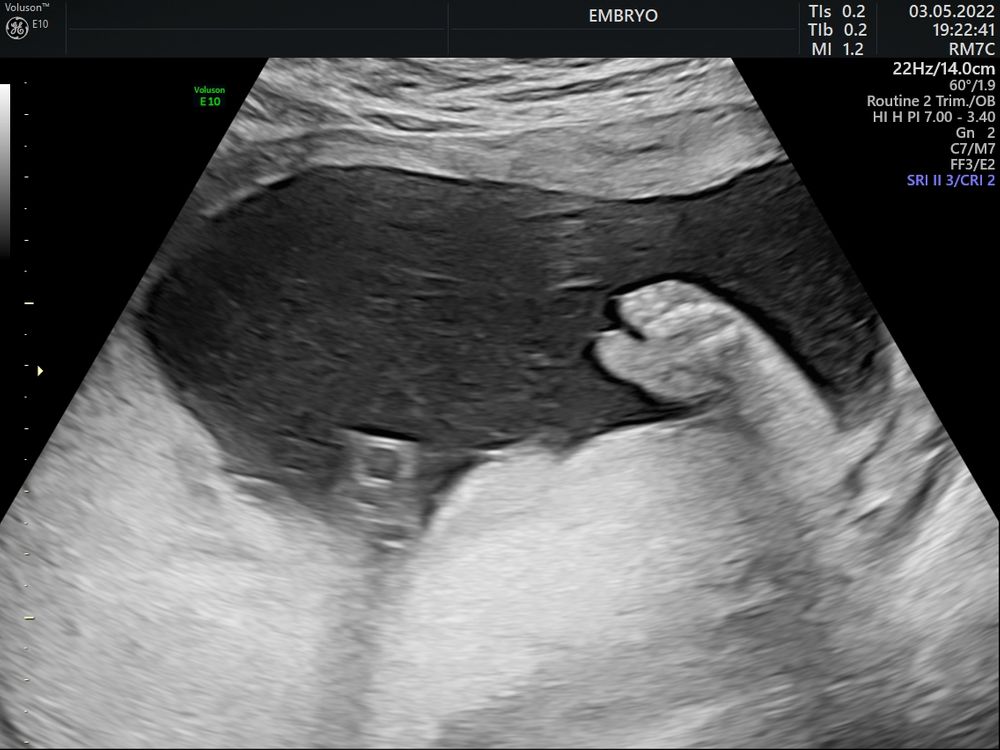

Пол малышаВсем привет, какова вероятность ошибки с полом на узи в 29 недель?

В 15, 17 и 21 - мальчик 100%

Яна, Вот и у меня все эти узи было очевидно что мальчик( фото прилагаю) , а сегодня ошарашили, думаю врач плохо посмотрела и все таки у нас пацан